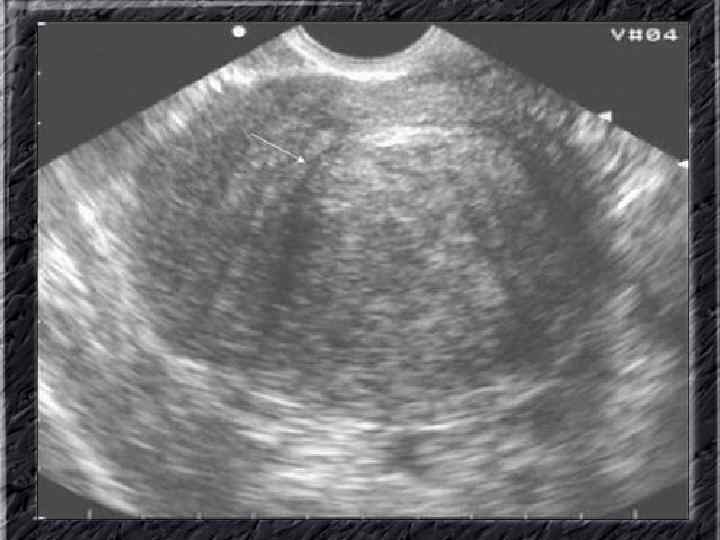

Названия слайдов: • • • Слайд 51. Ультрасонография: интерстициальный и истмический отделы маточной трубы. Слайд 52. Лапароскопия: неизмененная правая маточная труба. Слайд 53. Ультрасонография: многокамерная форма сальпингита. Слайд 54. Лапароскопия: относительно равномерное утолщение маточной трубы при гидросальпинксе. Слайд 55. Лапароскопия: вид маточной трубы при гидросальпинксе. Слайд 56. Гистеросальпингография: неравномерное расширение и деформация маточных труб. Слайд 57. Прервавшаяся трубная беременность: плод; макропрепарат. Слайд 58. Гематосальпингс, развившийся вследствие внутреннего разрыва плодо-вместилища при трубной беременности; макропрепарат. Слайд 59. Лапароскопия: значительное увеличение участка маточной трубы при трубной беременности. Слайд 60. Лапароскопия: скопление крови в полости малого таза в результате трубного аборта.